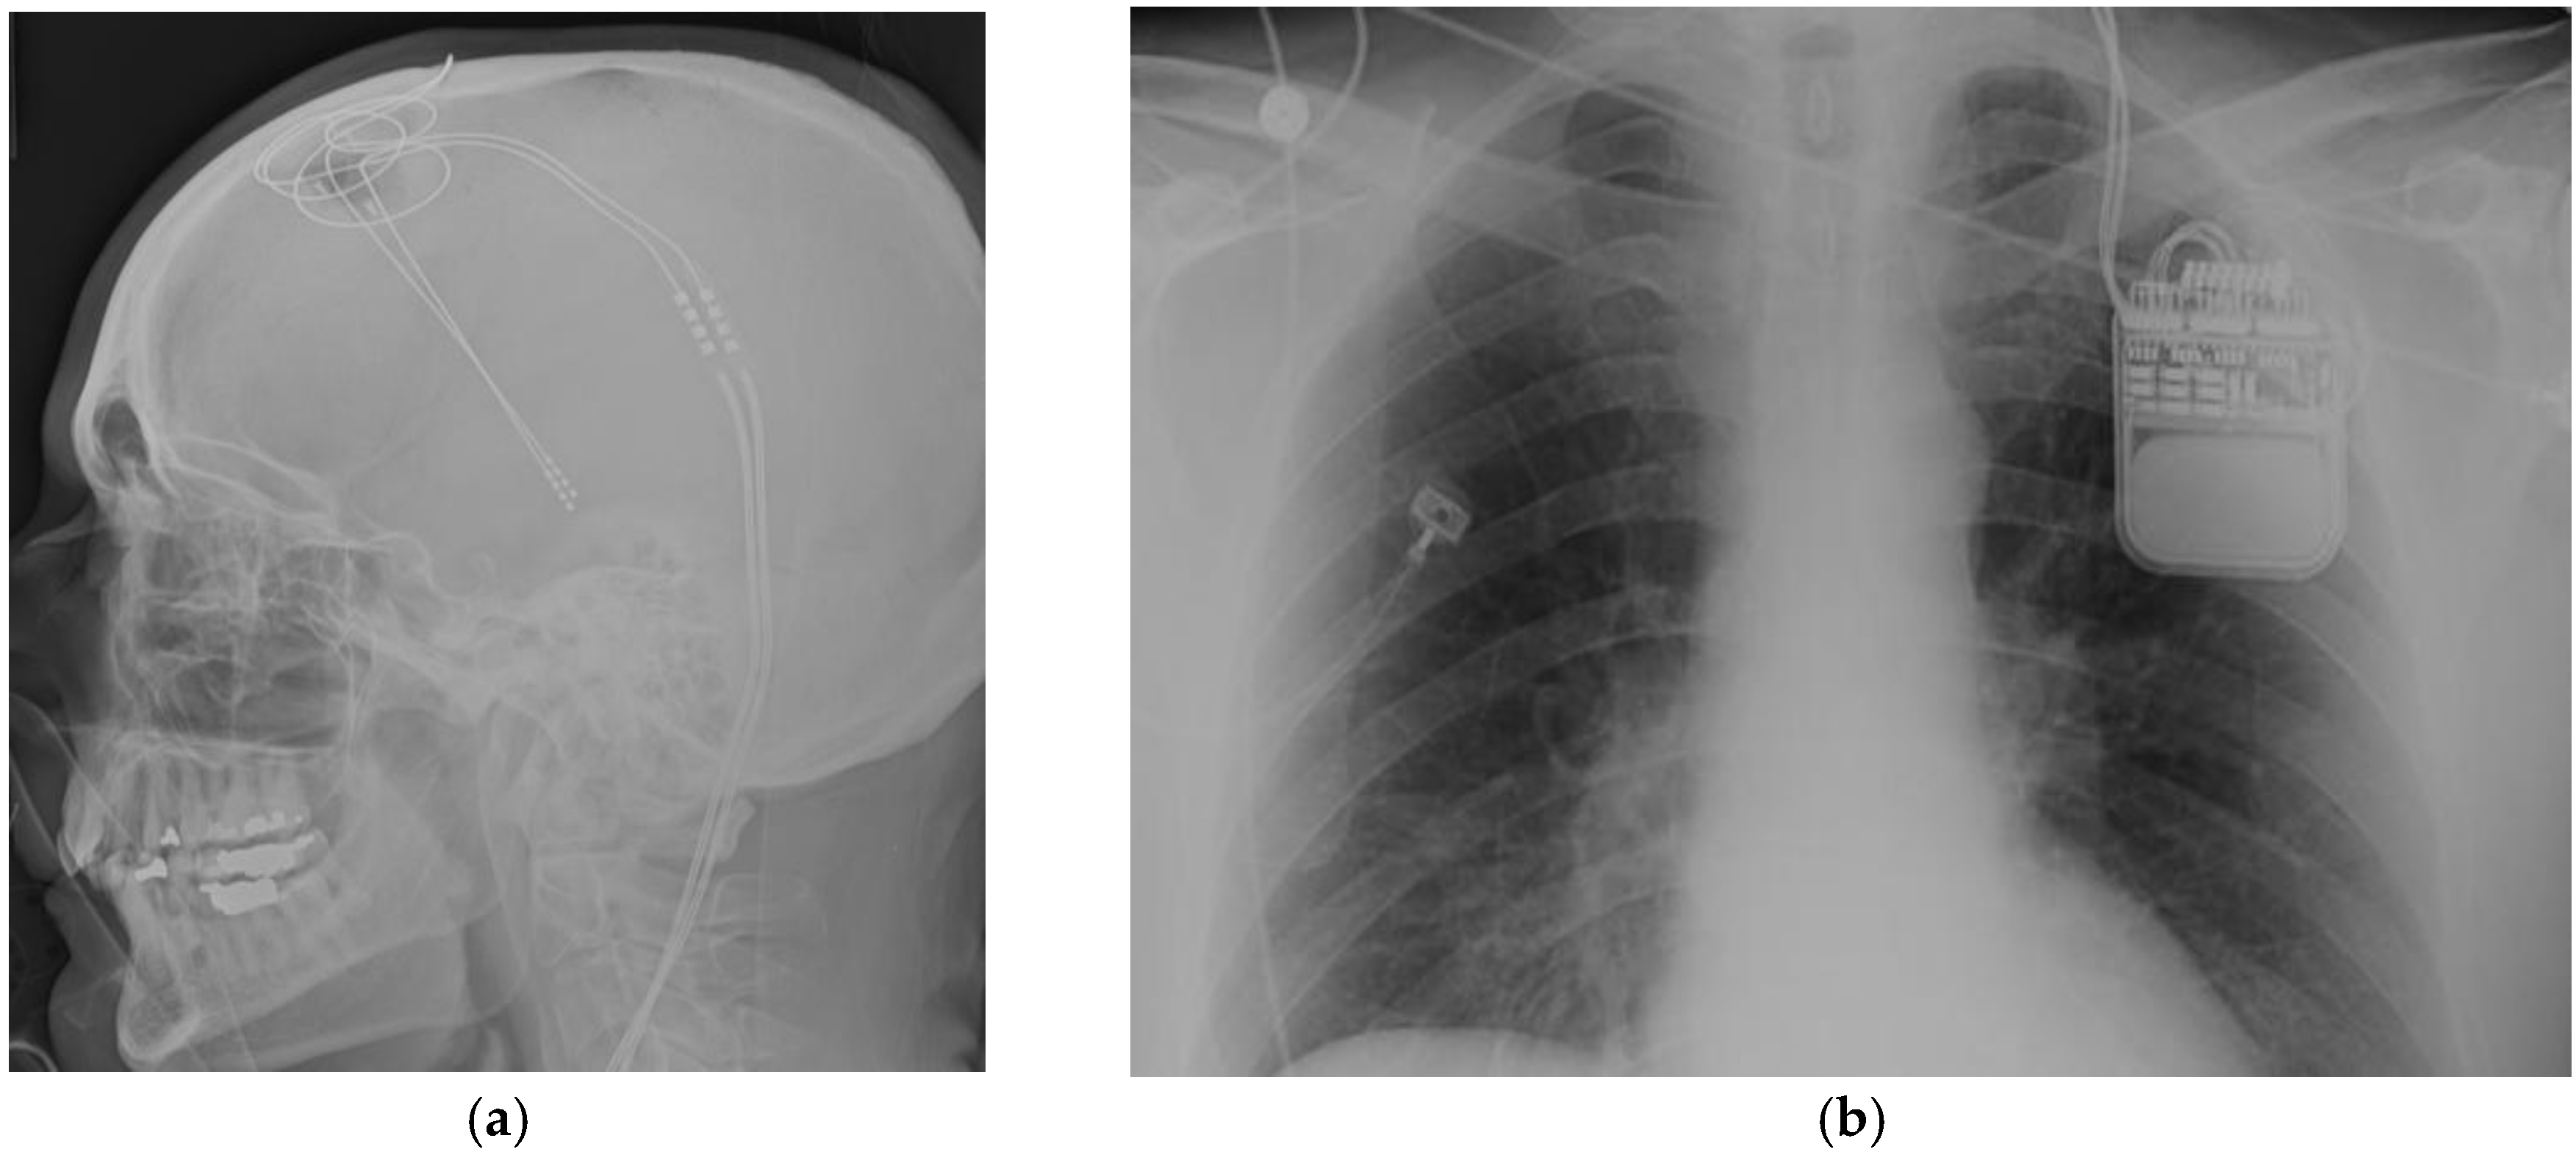

Figure 1.

(a) Lateral skull X-rays view of thalamic deep brain stimulator system; (b) Left infraclavicular implantable pulse generator.